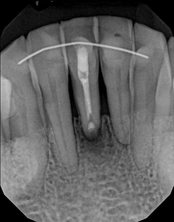

Non-surgical root canal treatment:

Before

After

6-month follow-upThe patient presented with mild pain, a cavity, and a broken filling was evident. After performing diagnostic testing, the diagnosis was: irreversible pulpitis, symptomatic periradicular periodontitis. Root canal therapy was done and the tooth healed well and is still functioning.